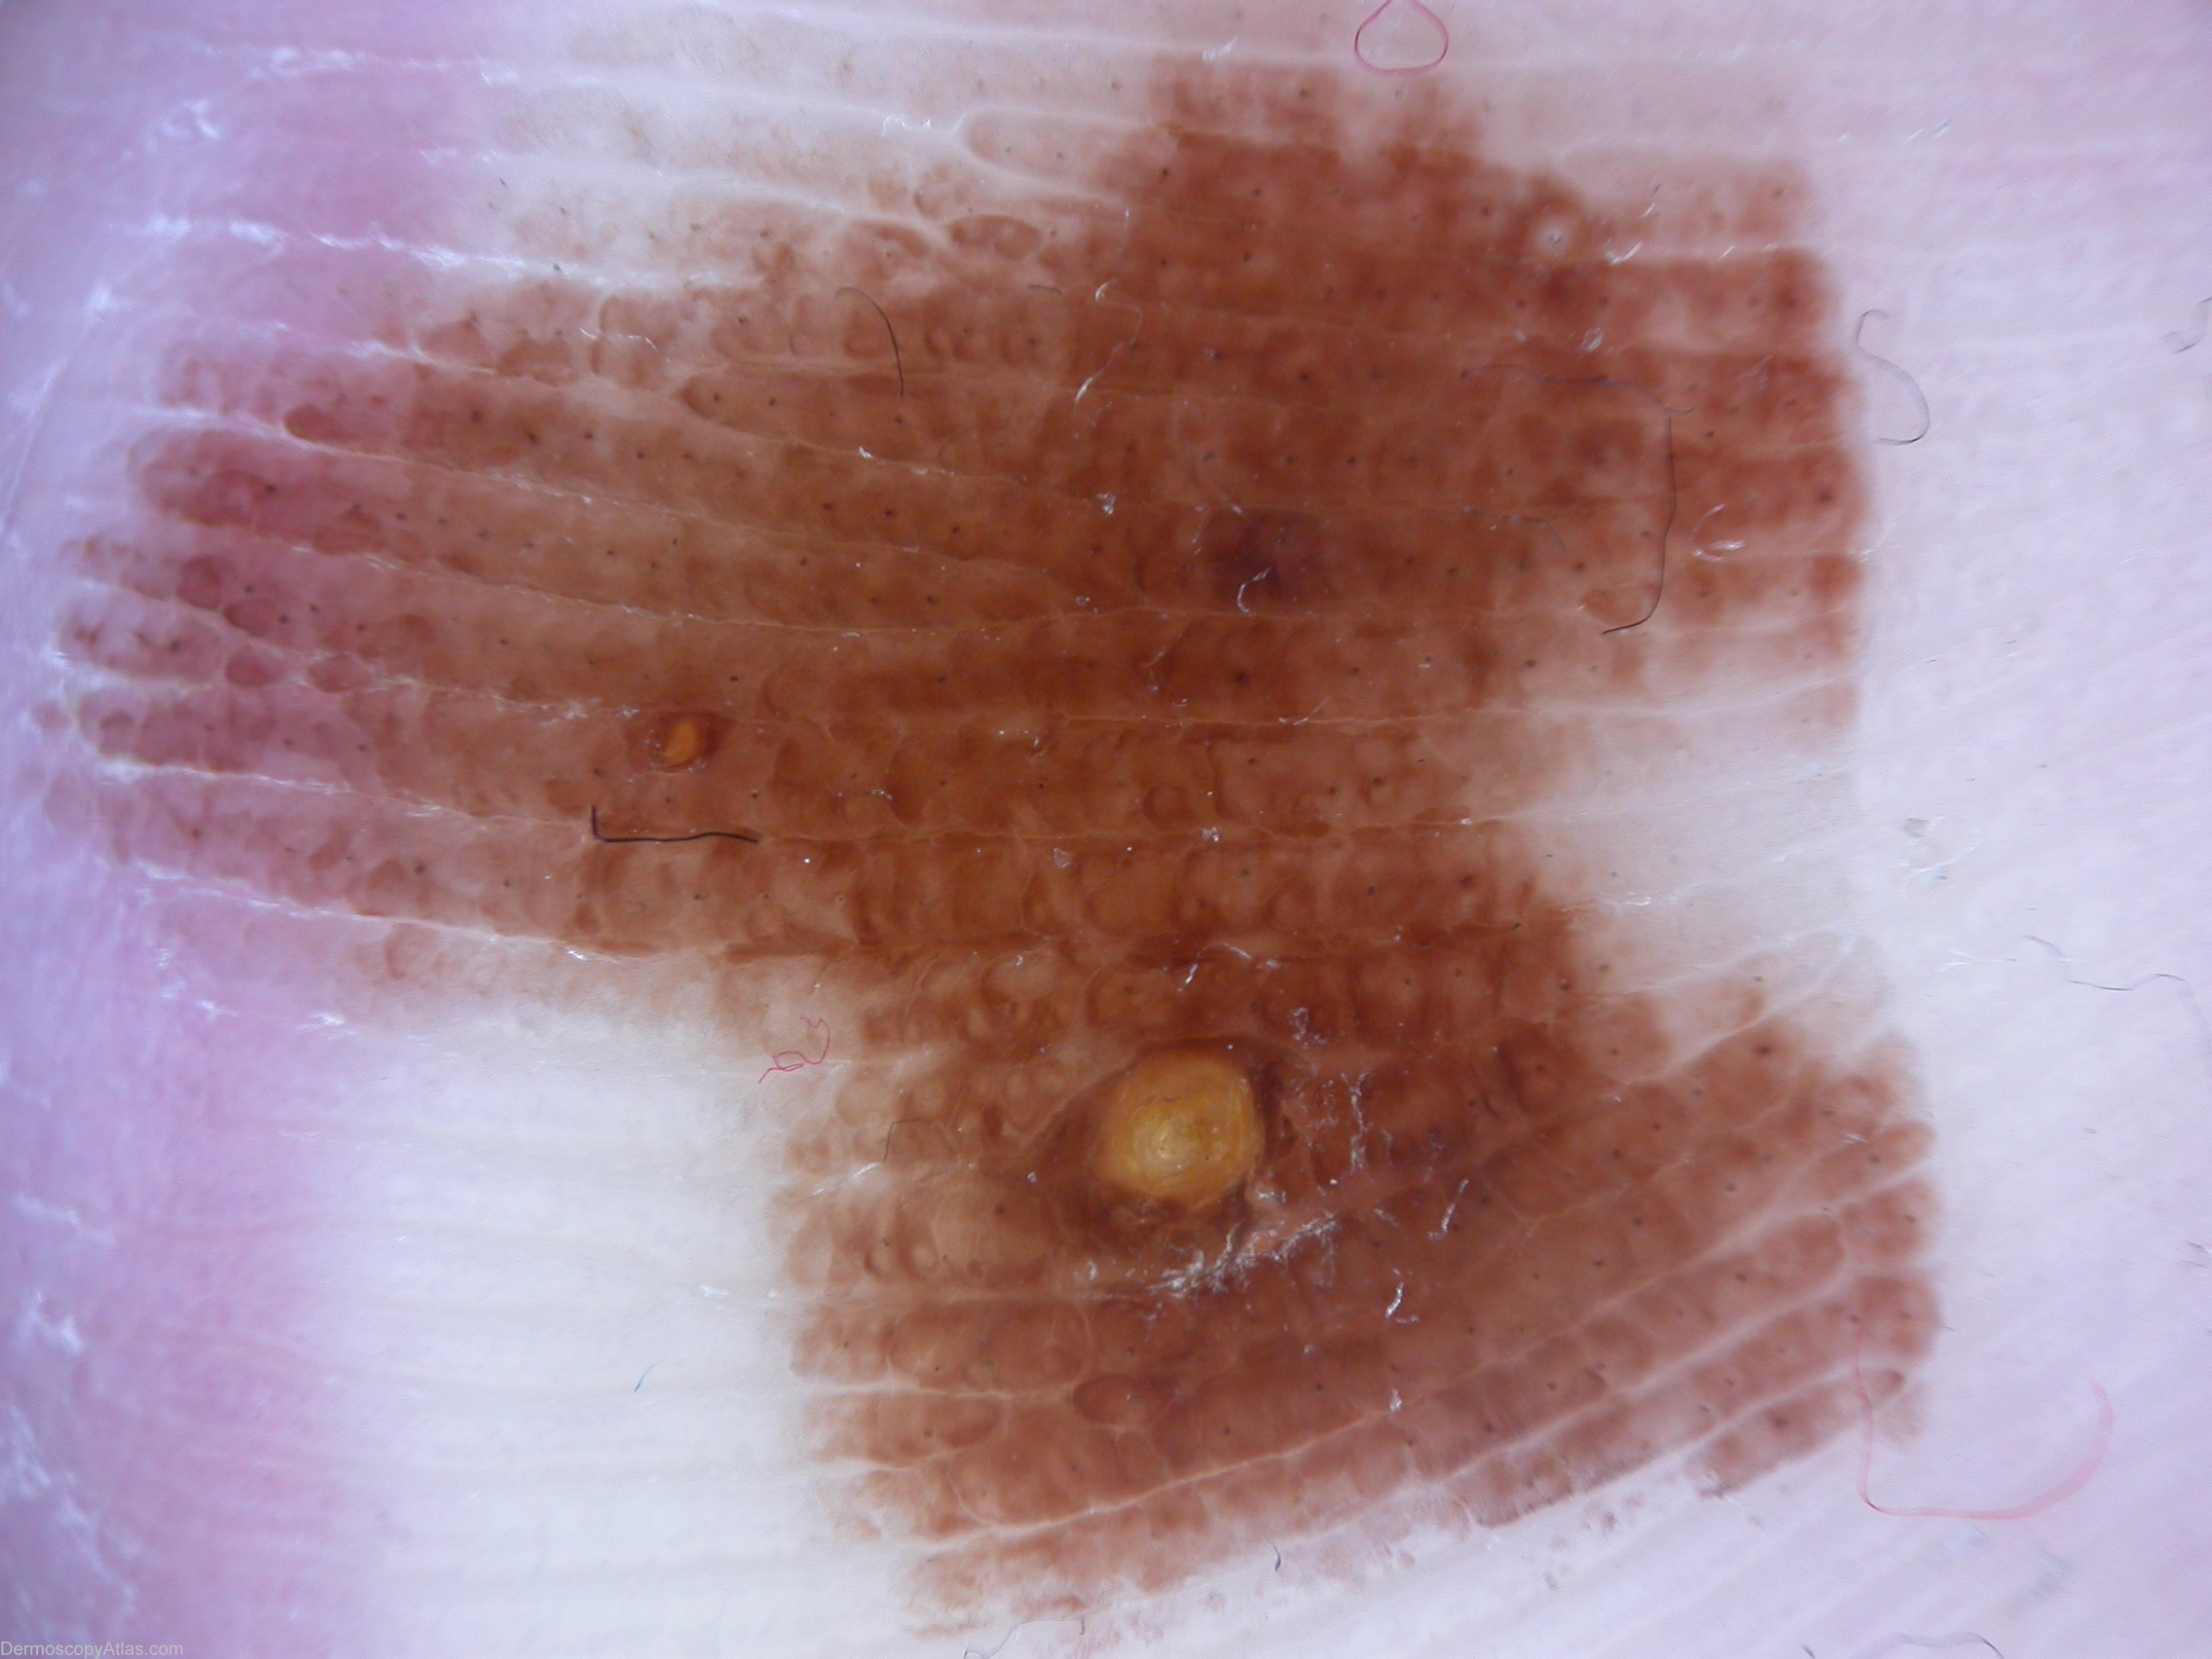

Diagnosis - Exogenous pigmentation

Diagnosis: Exogenous pigmentation